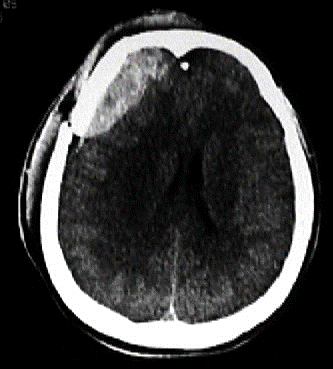

Diagnostic?

Hématome extra-dural droit